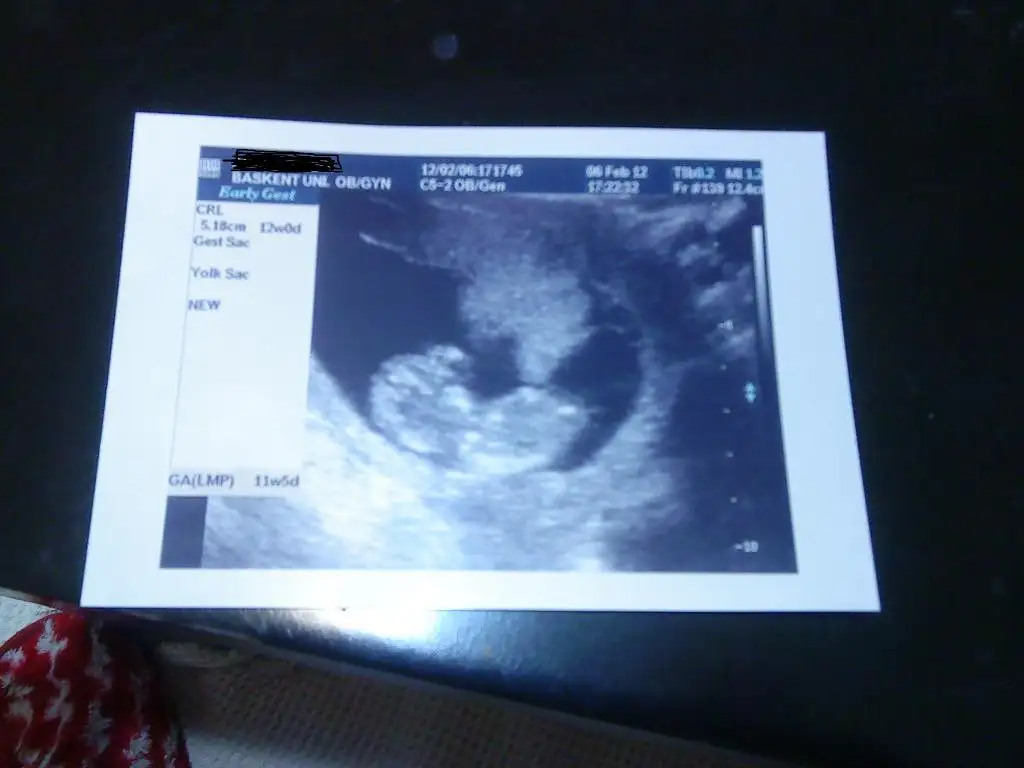

güzel arkadaşlarım ben geldim yemek işini halletmem gerektiği için yazamadım. bebişimi gördüm tosun gibi maşallah ama nasıl hareketli anlatamam.. eller..ayaklar hiç durmadan sallanıyo resmen bize doğru döndüğünü gördük, gözçukurlarını ağzını... ALLAHım sen ne büyüksen ben izlerken kendimden geçtim dr.un dediği hiçbişeyi anlamadım:)) ama çok şükür ölçümler normal çıktı kan testi de bir hafta sonra çıkıcak. rabbim herkeze tattırsın bu duyguyu..